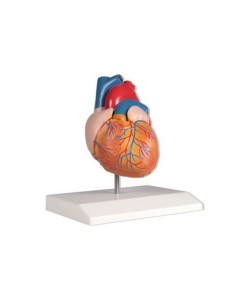

Des modèles anatomiques détaillés pour tous les besoins

Du crâne en 22 parties à verrouillage magnétique aux modèles de colonne vertébrale, des modèles d'articulation aux modèles de cœur, chaque pièce de notre collection est conçue pour une immersion totale dans l'étude de l'anatomie humaine. Nos modèles, réalisés à partir de scans d'os réels, garantissent une expérience tactile authentique et une fidélité de poids presque identique aux originaux.

Indispensables aux étudiants comme aux professionnels, nos modèles anatomiques sont des outils pédagogiques qui permettent d'observer les structures anatomiques avec précision, en évitant les dissections ou les études invasives. Ils sont également utiles pour expliquer les pathologies aux patients, ce qui rend la communication plus efficace et permet de gagner un temps précieux.